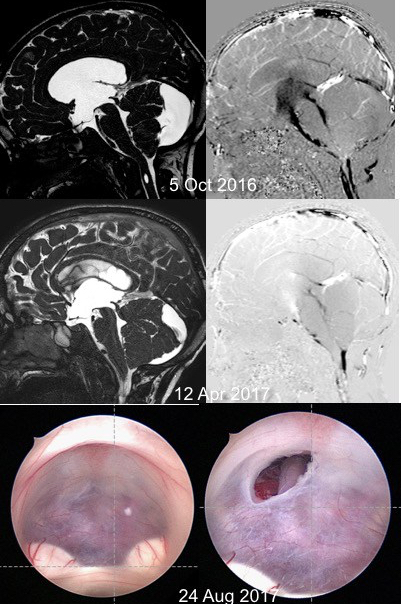

- l’échec secondaire est la refermeture d’une stomie qui a fonctionné de façon efficace. en cas d’échec secondaire, la meilleure solution est en général une nouvelle VCE. celle-ci a de bonnes chances de succès, évitant la pose d’une valve.

en cas d’échec secondaire, une nouvelle VCE a de bonnes chances de succès, comparables à celles d’une première opération (cf. ci-contre).

obstruction de la stomie

une obstruction de la stomie peut survenir jusqu’à 10 ans voire plus après l’intervention ; ceci justifie donc un suivi clinique et radiologique du patient au moins jusqu’à l’âge adulte.

le tableau clinique d’hypertension intra-crânienne peut être très trompeur, avec un patient qui va apparemment bien, mais qui va en fait mieux après l’intervention, et des cas dé dégradation dramatique avec mort subite. on est donc très interventionniste, même chez un patient asymptomatique, si l’imagerie montre un obstruction de la stomie.